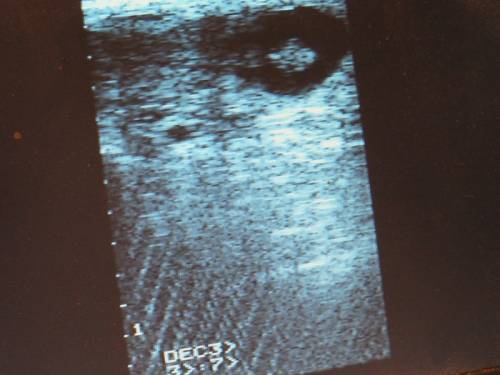

La grossesse de Diadème se poursuit très bien.

Échographie d'aujourd'hui: Le poulain est en haut à droite dans son “oeuf” situé en haut à droite de l'écran.

A comparer avec la semaine dernière:

Térence a fait un film. Dès que possible je vous le mets pour voir les battements cardiaques….